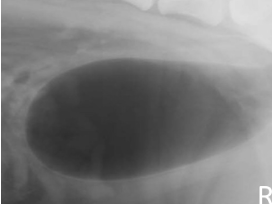

double contrast cystography highlights

mural diseases and intramural filling defects

intraluminal filling defects

3 types of free intraluminal defects bladder

calculi

hematoma, blood clot

gas bubbles